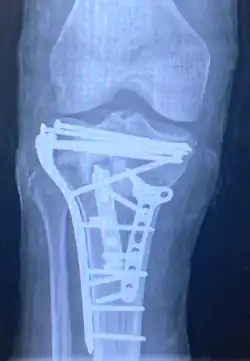

Repair of a tibial plateau fracture

Pain may be managed with NSAIDs, opioids, and splinting.[1][2] In those who are otherwise healthy, treatment is generally by surgery.[1] Occasionally, if the bones are well aligned and the ligaments of the knee are intact, people may be treated without surgery.[2] The surgery usually involves reducing the fractured fragments of the tibia plateau to their anatomical position and fixing them in place with screws only or fixed angle anatomical plates ensuring absolute stability. Implant selection is based on the type of injury. Generally, simple or incomplete fractures (Schatzker type 1) of the plateau are compressed with 6.5mm partially threaded cancellous screws. Complex type fractures will require a plate for enhanced stability. As the tibia condyles articulate with the femur (thigh bone) to form knee joint, any incongruity in the articular surface is unacceptable as it leads to early arthritis. Prolonged immobilization of the knee joint is also not recommended which result in stiffness of the joint and difficult recovery. Following a tibial plateau fracture, the patient is at risk for arthritis. This is referred to as post-traumatic arthritis. The more displaced the joint intra-articular surface is, the more likely post-traumatic arthritis is to occur. This occurs due to injury to the joint surface cartilage. When cartilage is damaged, arthritis can occur.[15] It's currently debated what role primary total knee arthroplasty (Joint Prosthesis) plays in the treatment of tibial plateau fractures. Although accompanied with risks small studies have shown promising results.[16]

A tibial plateau fracture requires orthopaedic surgical intervention for treatment. After X-ray and CT scans confirm fracture, Open Reduction Internal Fixation (ORIF) with medial and/or lateral plateau fixation is done. There are 5 different approaches that are most commonly used.[3]